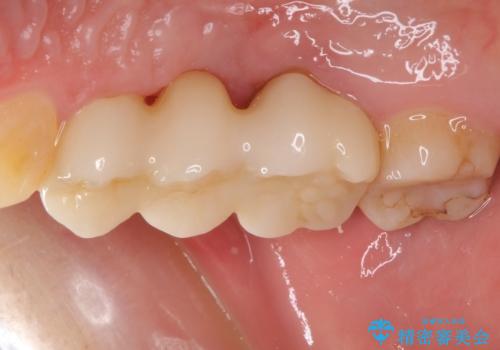

抜歯後に治癒を待って、フルジルコニアブリッジにて補綴することとしました。

抜歯をしたことで、ずっと気になっていた異臭から解放されました。

手前の歯を削ってブリッジ治療とするのか、インプラントによる治療とするのか、悩んでいらっしゃいましたが、奥歯の銀歯もセラミックにしたいとのことで、ブリッジ治療を選択されました。